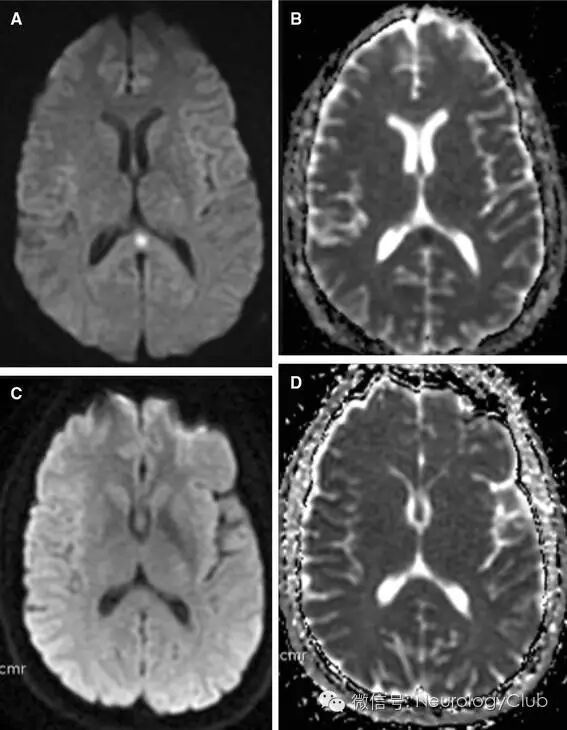

(图3:激素治疗相关的RESLES。A:T2WI高信号;B:FLAIR高信号;C:DWI高信号;D:ADC低信号;E:T1增强未见病灶强化;3周后病灶消失

(图4:激素治疗相关的RESLES。A:T2WI;B:FLAIR;C:DWI;D:ADC;3周后病灶消失